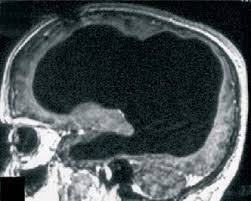

En 2007 se describió en Lancet el caso de un paciente francés de 44 años de edad que había acudido al hospital por un simple dolor en la pierna, dejando más tarde estupefactos a los médicos que estudiaron su escáneres cerebrales.

Y es que, en contra de todo pronóstico, las imágenes mostraron que gran parte de su cráneo estaba invadido por un líquido que había deteriorado todo su cerebro, dejando intacta sólo una fina región que no suponía más de un 10% del total.

La causa de este fenómeno podría ser la hidrocefalia, una enfermedad cuyo nombre lo dice todo, pero lo curioso es que a pesar de tener una proporción tan grande de su cerebro dañado, el paciente no mostraba los síntomas que deberían ser obvios. Tenía un cociente intelectual límite, de 75, pero no mostraba indicios de retraso mental y, de hecho, llevaba una vida normal, trabajando como funcionario, casado y con hijos.